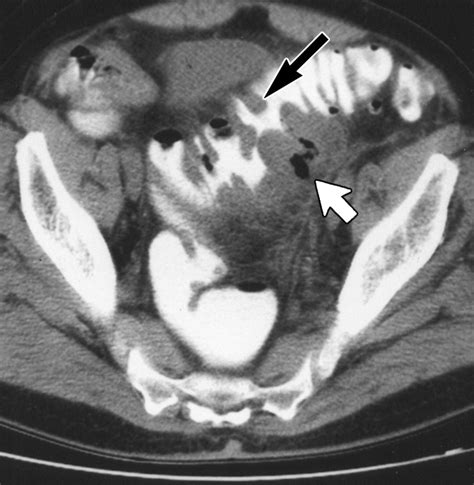

Diverticulitis is a painful condition that occurs when small pouches in the colon, known as diverticula, become inflamed or infected. When a patient presents with symptoms such as severe abdominal pain, fever, and changes in bowel habits, physicians must act quickly to make an accurate diagnosis. Among the various diagnostic tools available in modern medicine, a CT scan for diverticulitis is considered the gold standard. Its ability to provide detailed, cross-sectional images of the abdomen allows healthcare providers to confirm the presence of inflammation, assess the severity of the condition, and rule out other potential causes of abdominal distress.

• Complication Detection: It is highly effective at spotting complications such as abscesses, perforations, or fistulas.

Once the scan is completed, a radiologist will interpret the images and generate a report. If the scan confirms a diagnosis of diverticulitis, the radiologist will often grade the severity of the disease. This grading system is crucial for determining the appropriate course of treatment. The results of your CT scan for diverticulitis will likely focus on several key indicators:

• Wall Thickening: The degree to which the colon wall has thickened due to inflammation.

• Fat Stranding: A hazy appearance in the fat surrounding the colon, which is a classic sign of localized inflammation.

• Presence of Abscesses: Whether there are pockets of pus that may require drainage or specific antibiotic therapy.

• Free Air: A critical finding that may indicate a perforation, which is a medical emergency requiring immediate surgical consultation.